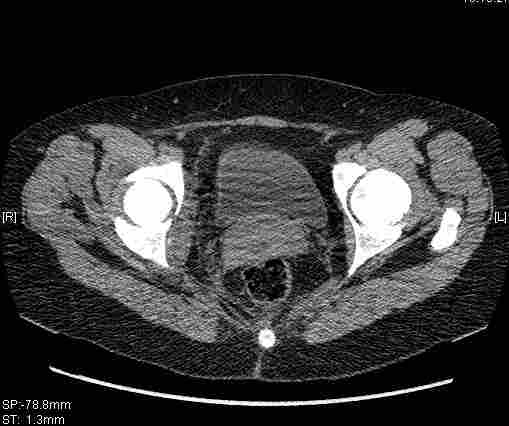

Удалось сегодня вывести пациентку в соседнюю больницу, где есть кт. Срезы сделаны только горизонтальные.

|

имеется передний подвывих, головка нагружаемой зоной будет "тереться" о край фрагмента, связанного с осевым скелетом.

вероятность быстрого прогрессирования коксартроза велика, хотя вряд ли кто-то укажет конкретные сроки. 1 год - 1,5 ?